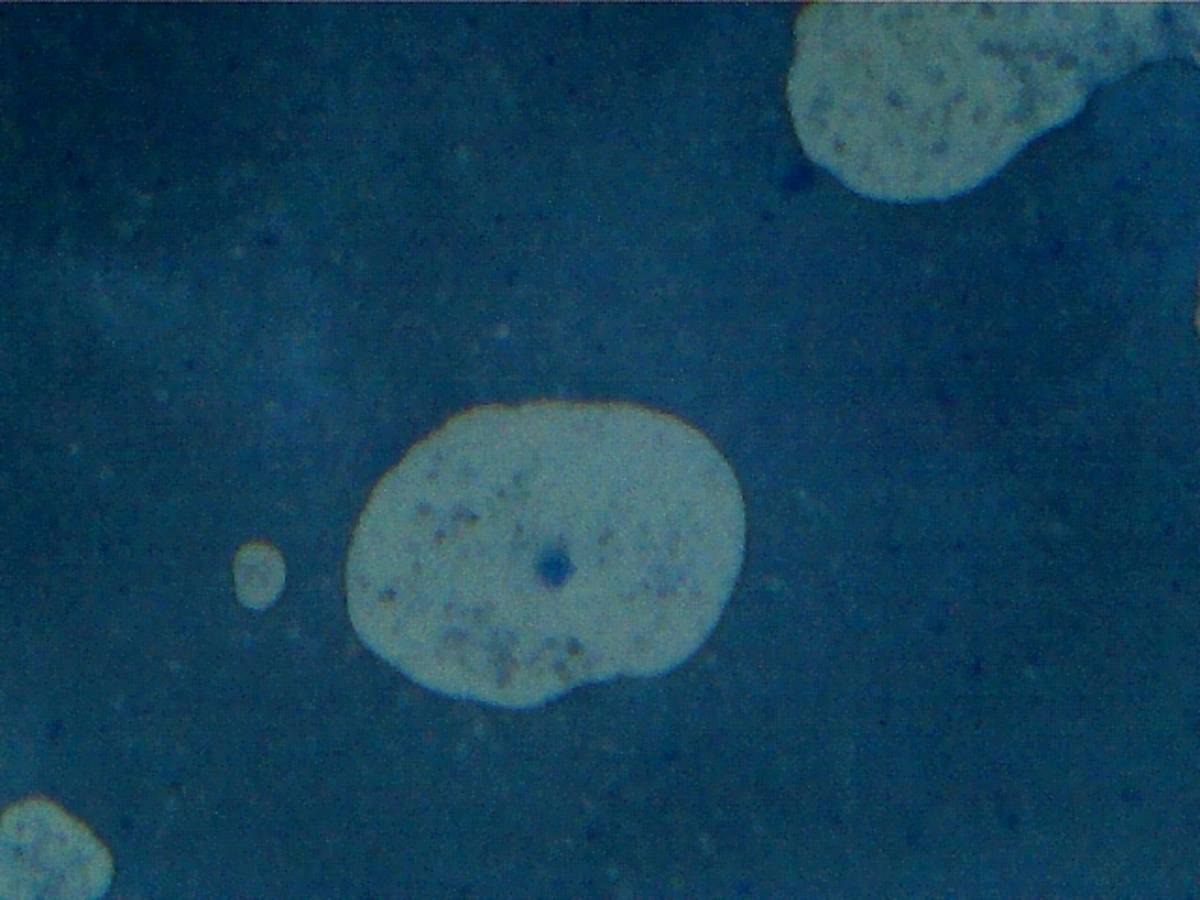

25 Fotografia Digitale, Paesaggio, Ritratto, Astratto informale, Digitale, 10x12.7cm Carta fotografica Digitale blood microscopic leukemia microscopic digital photography of my own Leukemia positive blood prior to treatment. Inserita 13 anni fa 1 Mi piace Non piace più 0 Commenti 156 Visite Condividi Facebook Twitter Google + Piace a 1 stefano venturini Artista - Como Commenti 0 Inserisci commento E' necessario effettuare il login o iscriversi per inserire il commento Login